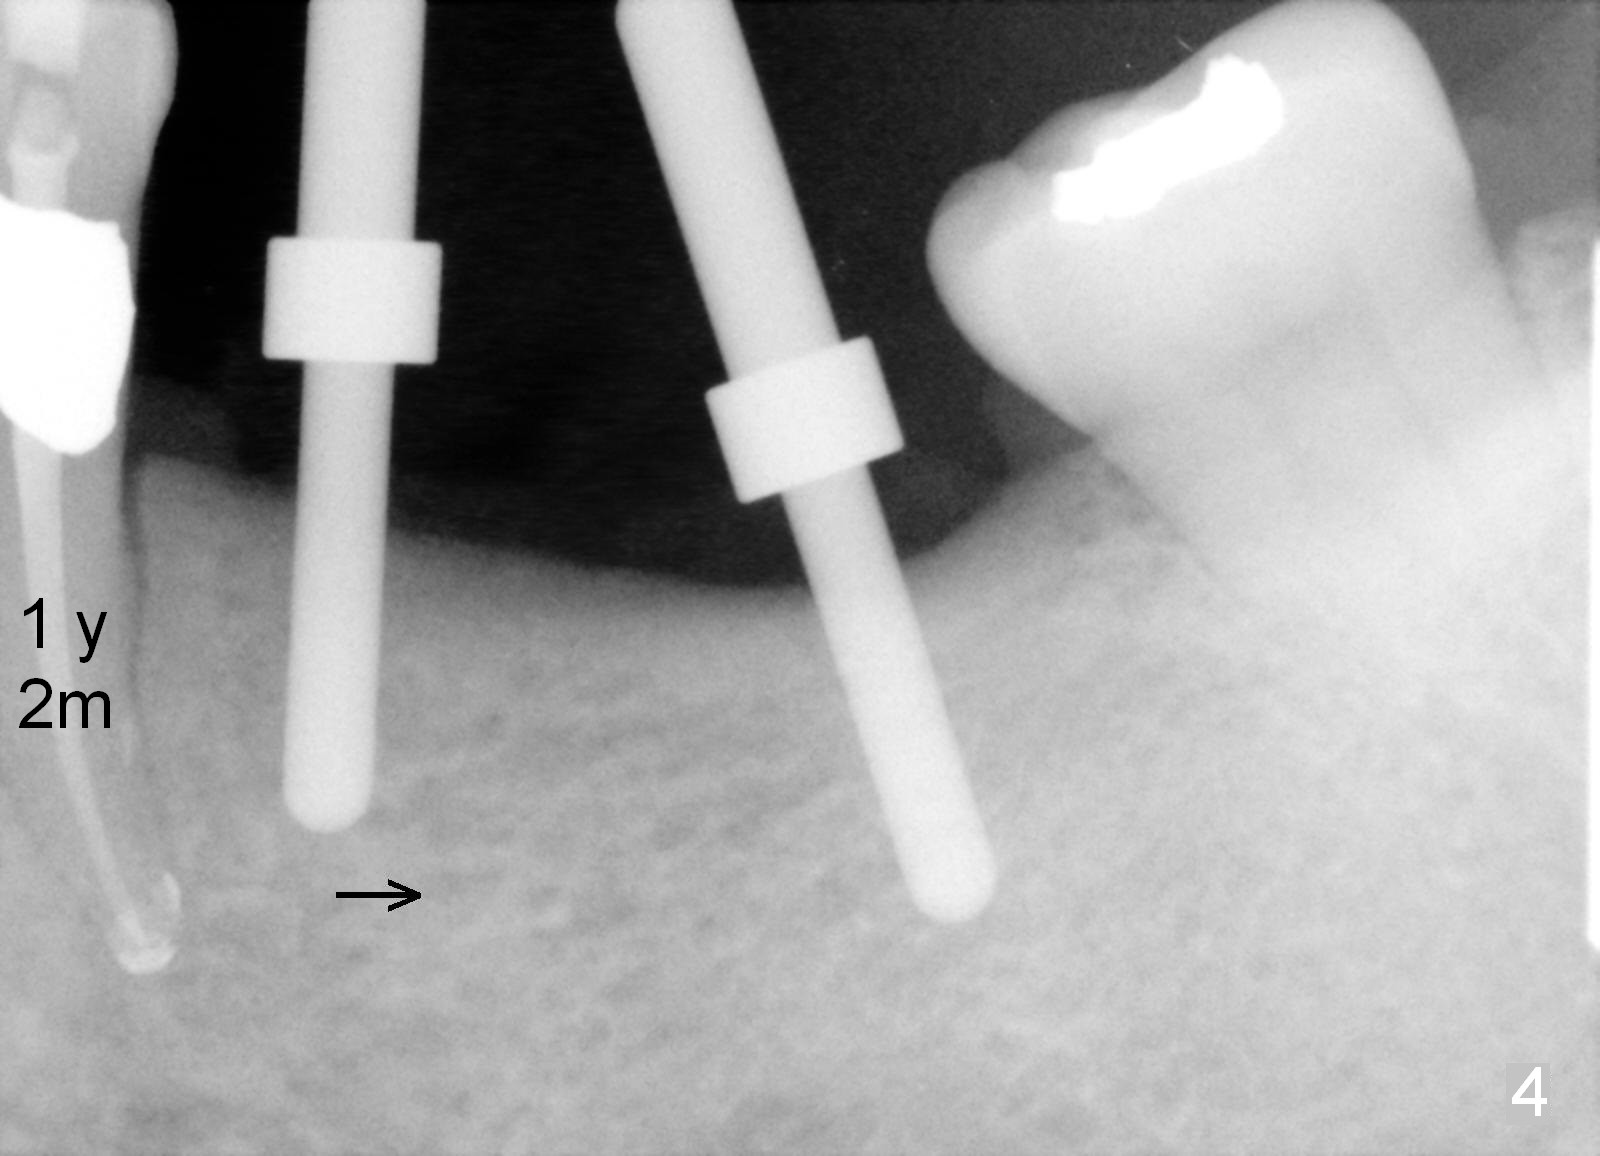

One year 2 months post root canal therapy at #20 (Fig.4), osteotomies are initiated at #18 and 19. The trajectory at #19 is subsequently corrected (Fig.5); that of #18 should be also corrected (arrow). The fact of the narrow ridge (Fig.6) is also ignored intraop. Without further adjustment, the osteotomies are enlarged (Fig.7) and the implants are placed (Fig.8: 4.5x14, 5x14 mm). As expected, the buccal coronal implant surface is exposed. The buccal plate is decorticated with placement of autogenous bone graft. Periodontal dressing is applied. Postop, the wound is infected with wound gapping. With irrigation, the wound finally heals.